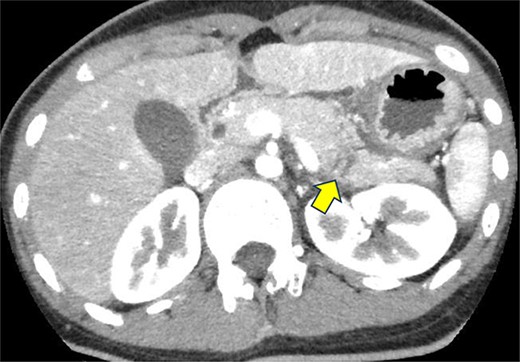

On the fifth day, the ascitic fluid increased in volume, and an open distal pancreatectomy was considered. However, her condition was stable. CT-guided abdominal drainage was performed, and a 10 Fr drainage tube was inserted for peritoneal lavage (Fig. 4). EUS-guided transgastric drainage of the pseudocyst in the omental bursa was performed. The pseudocyst was punctured; a balloon was dilated through the posterior wall of the stomach (Fig. 5a–c), and three tube stents of 7 Fr were implanted (Fig. 5d). The Amy and P-Amy levels in ascites were 9429 and 8877 IU/L, respectively; then, peritoneal lavage was performed daily. On the 12th day, contrast-enhanced CT revealed reduced pseudocyst size (Fig. 6). The patient was discharged on the 16th day (Fig. 7). Three years later, the patient is living her daily life without any complications.

Contrast-enhanced CT on the 12th day. The pseudocyst in the omental bursa had shrunk. The arrow indicates the pseudocyst.